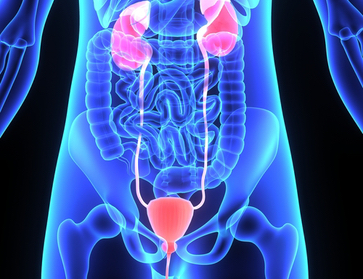

Uro

gyne

cology

Urology